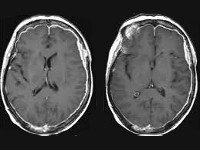

• МРТ головного мозга. Диагностирует гидроцефалию, при наличии масс-эффекта - смещение мозговых структур. Определяет повышение плотности оболочек, наличие в них мелких очагов. Более информативна МРТ с контрастированием, позволяющая выявить накопление контраста в оболочечных тканях, субарахноидальных пространствах.